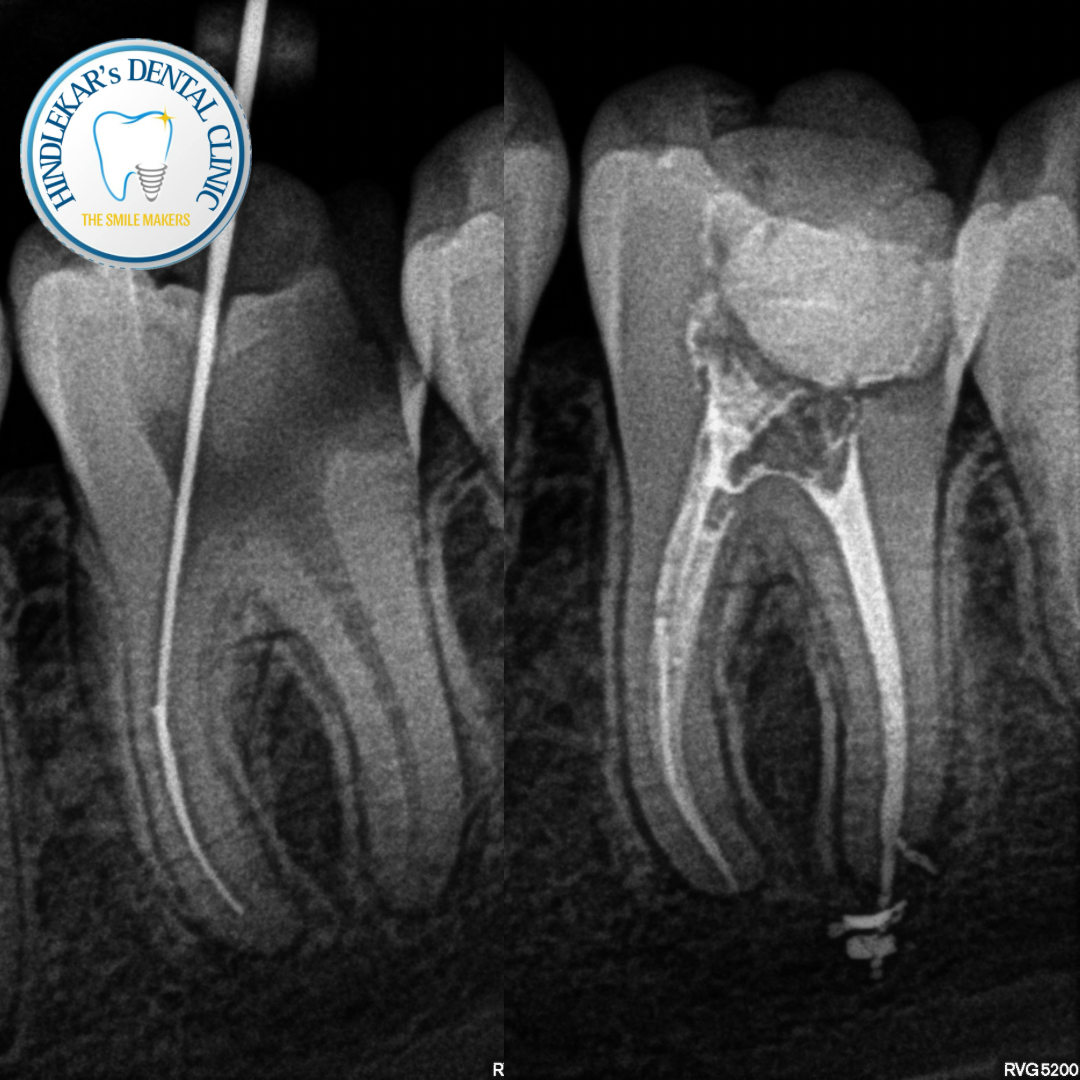

❗ Persistent pain after RCT?

❗ Swelling or infection?

✔ Re-treatment cases

✔ Complex root canals